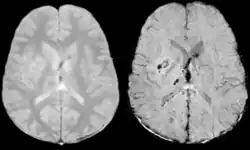

Gradient recalled echo (GRE) imaging is the conventional way to detect hemorrhage in CAA, however SWI is a much more sensitive technique that can reveal many micro-hemorrhages that are missed on GRE images.[7] A conventional gradient echo T2*-weighted image (left, TE=20 ms) shows some low-signal foci associated with CAA. On the other hand, an SWI image (center, with a resolution of 0.5 mm x 0.5 mm x 2.0 mm, projected over 8mm) shows many more associated low-signal foci. Phase images were used to enhance the effect of the local hemosiderin build-up. An example phase image (right) with yet higher resolution of 0.25 mm x 0.25 mm x 2.0 mm shows a clear ability to localize multiple CAA-associated foci.